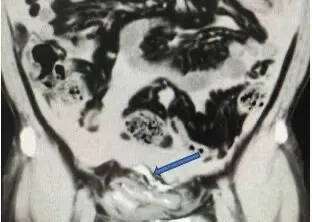

急诊团队迅速为张先生实施导尿并进行腹部CT检查,同时联系泌尿外科团队进行病例讨论。影像结果显示,本应存在于膀胱内的造影剂竟出现于腹腔中,结合患者腹部受击打、大量饮酒后长时间憋尿的病史,确诊为膀胱破裂。

箭头处可见外渗进腹腔的造影剂